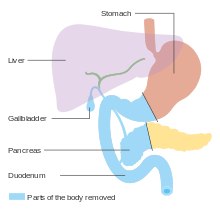

For cancers involving the head of the pancreas, the Whipple procedure is the most commonly attempted curative surgical treatment. This is a major operation which involves removing the pancreatic head and the curve of the duodenum together ("pancreato-duodenectomy"), making a bypass for food from the stomach to the jejunum ("gastro-jejunostomy") and attaching a loop of jejunum to the cystic duct to drain bile ("cholecysto-jejunostomy"). It can be performed only if the person is likely to survive major surgery and if the cancer is localized without invading local structures or metastasizing. It can therefore be performed only in a minority of cases. Cancers of the tail of the pancreas can be resected using a procedure known as a distal pancreatectomy, which often also entails removal of the spleen.[4][6] Nowadays, this can often be done using minimally invasive surgery.[4][6]